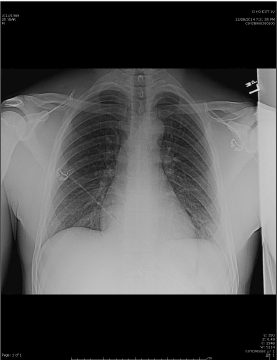

On arrival to the hospital, his BP was 135/74, HR 77, RR 20, and Pulse Ox was 94%.  His pain score was 9 of 10. His physical examination was remarkable for an abrasion along the left anterior chest wall. There was no deformity, crepitance, or instability.  The area was tender, but visual contusion had not yet developed.  Breath sounds were full and equal bilaterally.  A portable chest x-ray revealed mild ground-glass opacity of the left lung base with obscuration of the lateral left hemidiaphragm (figure 1).

Figure 1. A portable chest x-ray revealed mild ground-glass opacity of the left lung base with obscuration of the lateral left hemidiaphragm.